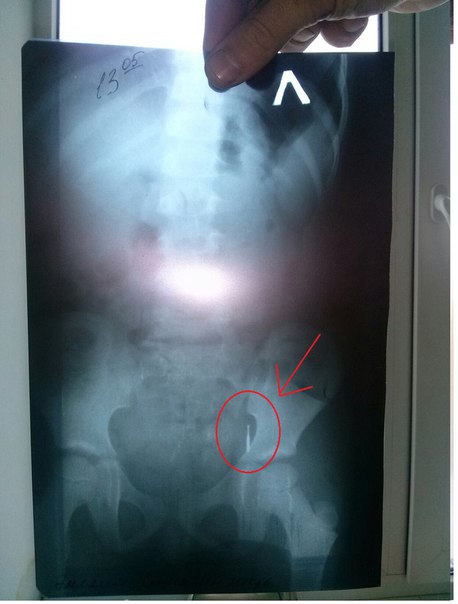

Мы уже сообщали о ЧП, произошедшем в государственной стоматологии. Родители сообщили, что после лечения зуба у ребенка в желудке оказался бур небольшого размера.